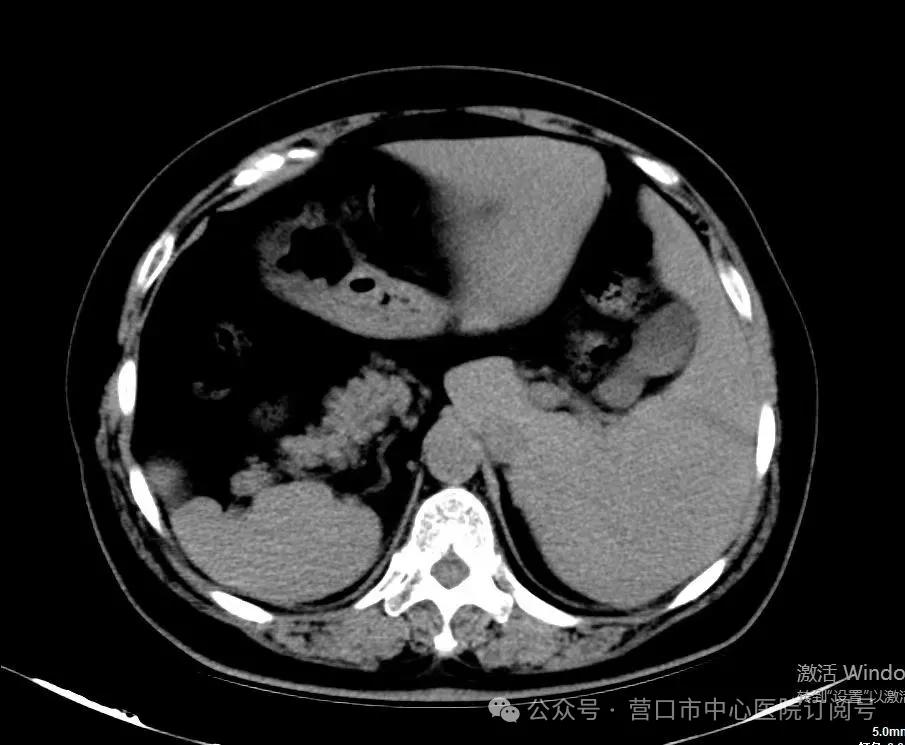

近日,营口市中心医院普外三科团队成功完成一例极特别的腹腔镜下胆囊切除手术。患者是一位罕见的“镜面人”,心肺肝胆胃肠全部反着长。内脏反位发生率据不完全统计大约为0.0001%。该患者因“胆囊息肉”到市中心医院就诊,查腹部彩超提示胆囊位于左侧肝下,胆囊息肉,直径大于1cm,具备胆囊切除手术指征,收入院行手术治疗。

由于消化系统具有不对称性,内脏反位患者解剖关系与常规习惯相违背,手术不仅仅是“换一个方向做”就行,需要医生在“逆向思维”的引导下,转变站位、操作方式、习惯、器械使用方向等,极大增加了手术风险及操作难度,稍有不慎,可能会引发胆道损伤、腹腔感染等并发症。为确保手术安全,术前由于志勇主任领导的普外三科医生团队针对患者病情进行了专题讨论,分析术中的疑点难点,确定肝脏、胆囊等脏器的精准位置,做好充分的手术预案和技术探讨。由于志勇主任领导的普外三科医生团队克服重重困难,顺利完成手术,手术用时不足1小时,3天后患者康复出院。